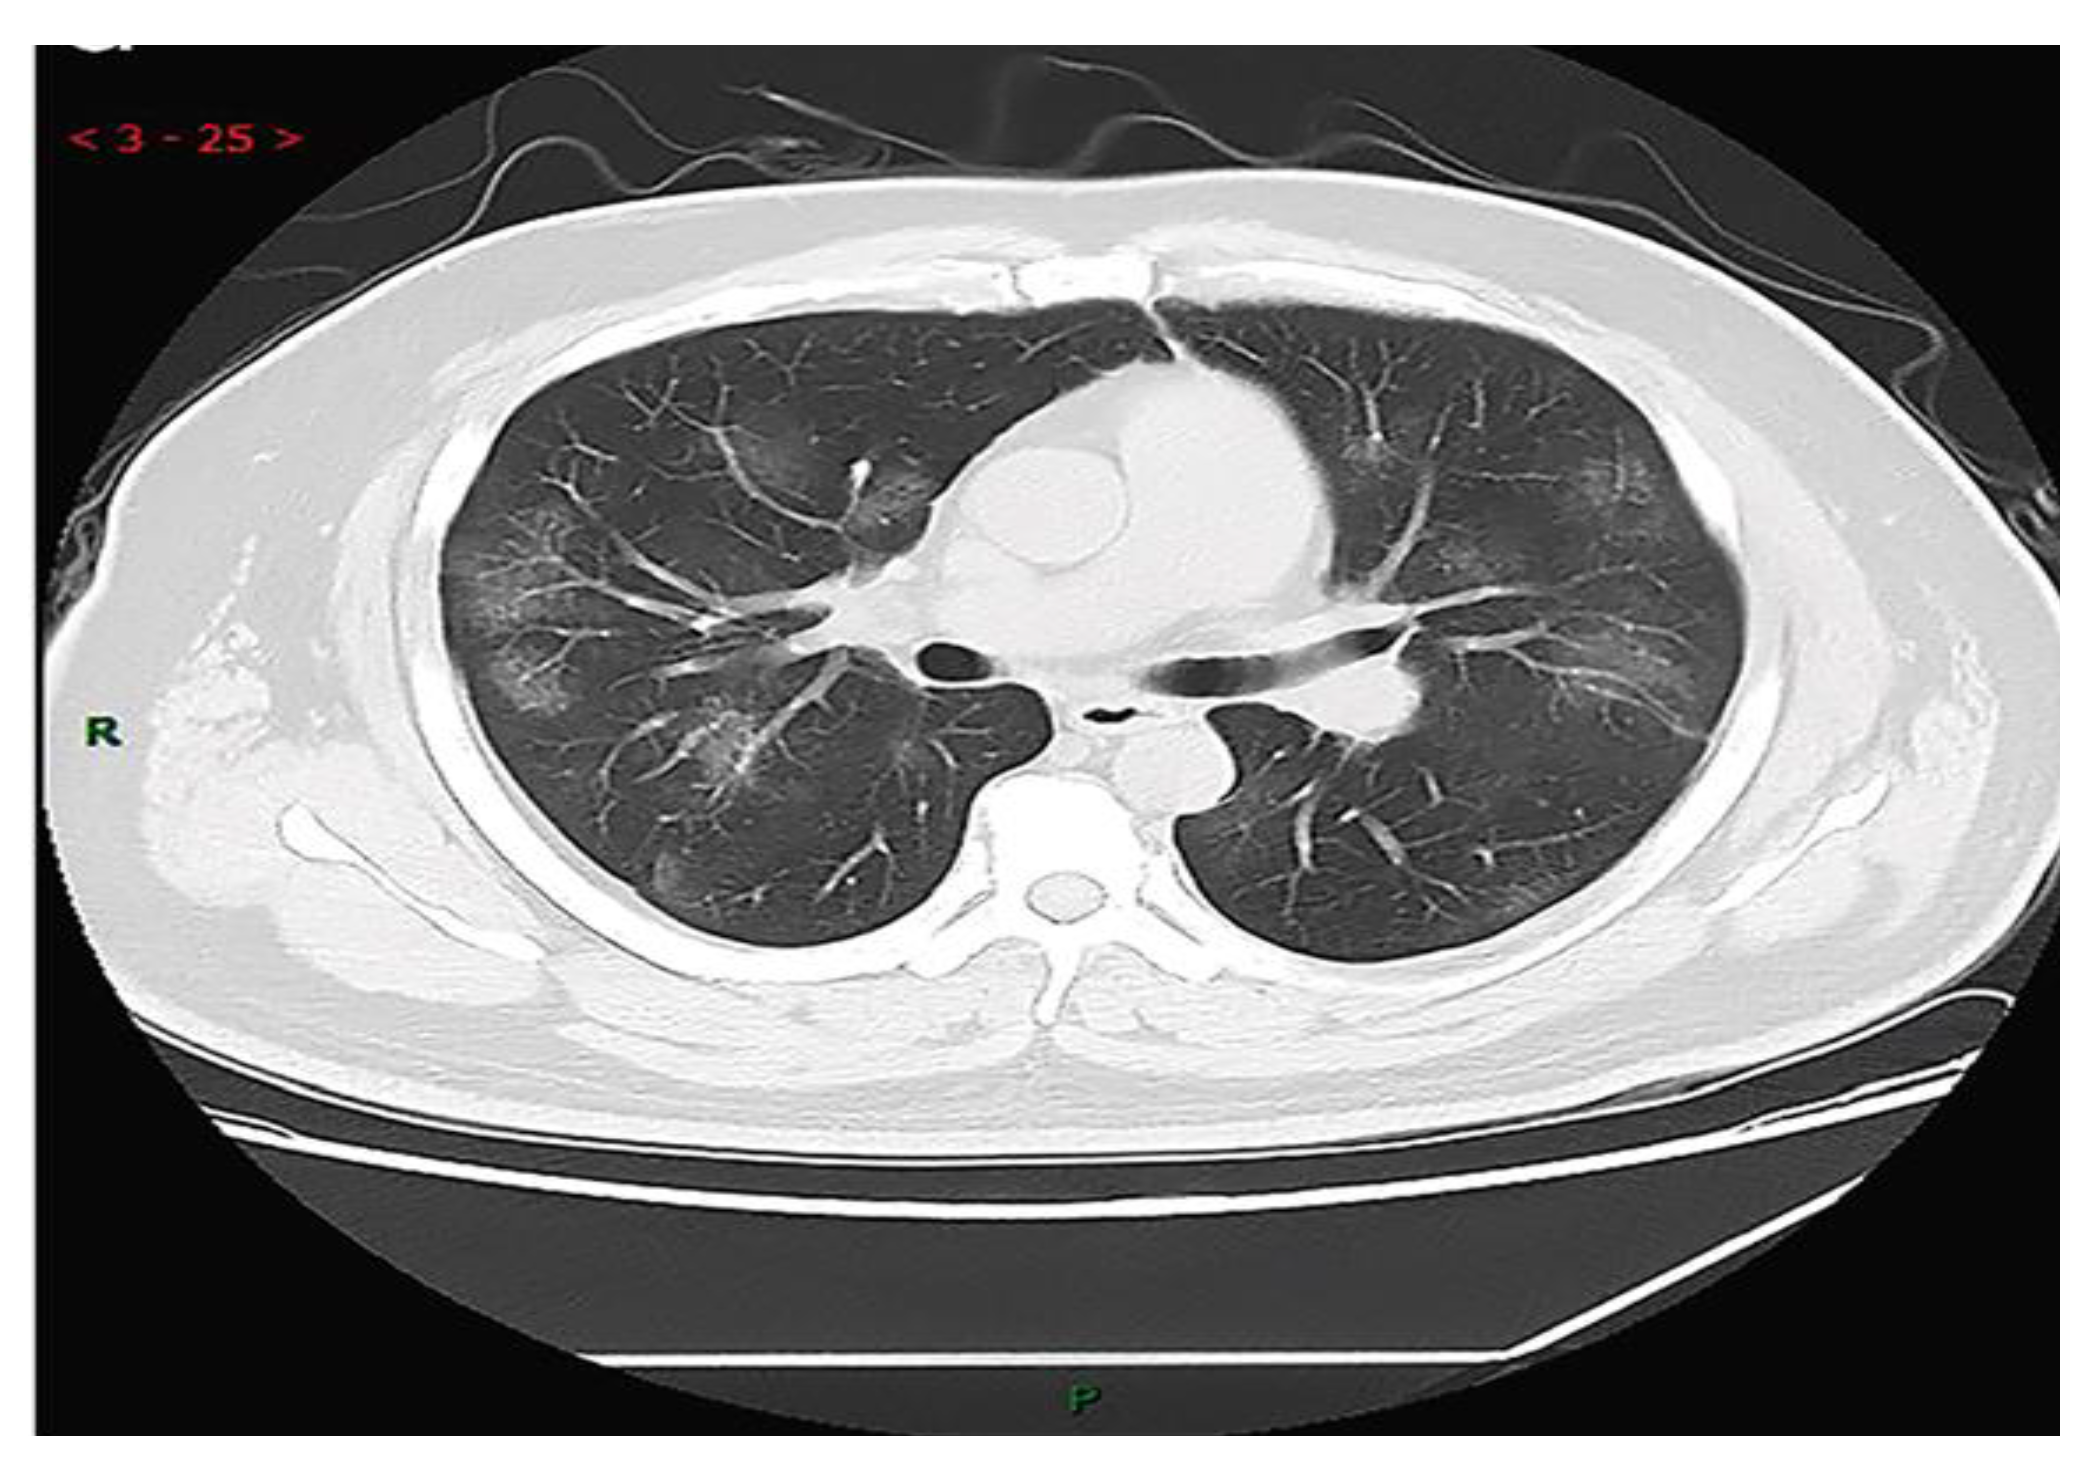

The chest CT scans testing method is one of the most useful methods for the detection of COID-19 along with laboratory testing methods such as PCR, hematology tests, and rRT-PCR. In this regard, Y. H. Jin et al [1] strongly suggested CT imaging for the diagnosis of COIVD-19. They reported that in the CT images of 54.2% COVID-19 patients, multiple, patchy, sub-segmental or segmental ground-glass density shadows in both lungs were observed (Figure 1). They also noted that the CT scans of 31.3% of severe patients infected with COVID-19 showed the patchy, multiple, and/or large patches of consolidation in lungs along with a honeycomb-shaped interlobular septal thickening or little grid-like in the lower and middle lobes.

Figure 1. CT image of 38 years old male with fever (39.3℃), dry cough and shortness of breath for 3 days (adopted from Y. H. Jin et al., 2020 [1]).